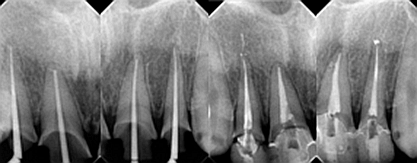

下面是醫(yī)生眼中和ct下的我們

一身病痛啊

牙結(jié)石、牙齦炎癥、牙體殘缺、慢性牙髓炎、蛀牙......